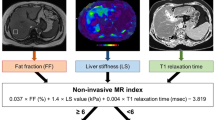

This retrospective study included 53 patients. Histogram and texture parameters (volume, mean, SD, median, 5th percentile, 95th percentile, skewness, kurtosis, diff-entropy, diff-variance, contrast, and entropy) of T1 maps were calculated based on the semi-automatically segmented whole-liver volume. A two-step approach combining the Nonalcoholic Fatty Liver Disease Fibrosis Score (NFS) and Fibrosis-4 Index (FIB-4) with the liver stiffness measurement (LSM) for the risk stratification was used. Univariate analysis was performed to identify significant parameters. Logistic regression models were then run on the significant features. Diagnostic performance was evaluated with receiver operating characteristic (ROC) analysis.

The Nonalcoholic Fatty Liver Disease Fibrosis Score (NFS) was calculated using the following formula: − 1.675 + 0.037 × age (years) + 0.094 × body mass index (kg/m2) + 1.13 × impaired glucose tolerance or diabetes mellitus (yes = 1, no = 0) + 0.99 × aspartate aminotransferase to alanine aminotransferase ratio − 0.013 × platelet (109/L) − 0.66 × albumin (g/dL).

The Fibrosis-4 Index (FIB4) was calculated using the following formula: age (years) × aspartate aminotransferase/[platelet (109/L) × square root (alanine aminotransferase)].

Liver stiffness measurements were performed using vibration-controlled transient elastography technology (FibroScan device; Echosens), using an M probe.

The approach uses NFS or FIB-4 [18, 19] as the first-line procedure (Fig. 1): Patients with FIB-4 < 1.3 or NFS < − 1.455 were considered to be at low risk of advanced fibrosis; patients with FIB-4 = 1.3 to 3.25 or NFS = − 1.455 to 0.672 were considered to be at intermediate risk, patients with FIB-4 > 3.25 or NFS > 0.672 were considered to be at high risk of having advanced fibrosis.

When the first-line test showed an intermediate or high risk, a second-line evaluation of LSM was performed: an LSM of less than 8 kPa was considered to be low, 8 kPa~10 kPa was considered intermediate, and 10 kPa or greater was considered to be a high risk of having advanced fibrosis.